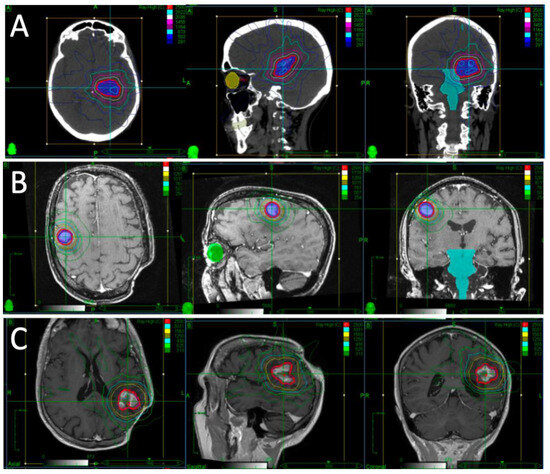

A patient presented with falls, short-term memory loss and word-finding difficulties. An MRI revealed a 4.6 × 4.2 × 4.0 cm mass centered in the left thalamus. Due to the rapid progression of symptoms and development of hemiplegia, they underwent partial resection. Pathology revealed diffuse large B-cell lymphoma (DLBCL). They proceeded to receive two cycles of high-dose methotrexate and cytarabine but had progression while on chemotherapy, with MRI demonstrating a 1.8 × 1.2 cm enhancing lesion in the left middle cerebral peduncle and thalamus. Their KPS was 30–40. After multidisciplinary discussion, it was decided to proceed with fSRS to this lesion. Representative images of their fSRS are shown in Figure 1. fSRS was completed 3 months after their partial resection and 2 months after their last chemotherapy. They had a complete radiologic remission and regained much of their neurologic function, with some residual fatigue and right-sided weakness and sensory deficits.

Figure 1. Target volumes and dose distribution for Case 1, outlining their first (A), second (B), and third (C) courses of fSRS. Repeat fSRS was necessary due to regional recurrences, but no in-field recurrences were noted in their case. The red isodose line represents the prescription dose of 25Gy.